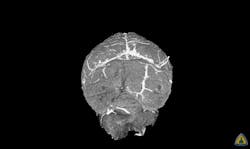

Johns Hopkins Medicine researchers have developed and tested a new imaging approach they say will accelerate imaging-based research in the lab by allowing investigators to capture images of blood vessels at different spatial scales according to a new report.

The method, dubbed “VascuViz,” includes a quick-setting polymer mixture to fill blood vessels and make them visible in multiple imaging techniques. The approach enables researchers to visualize the structure of a tissue’s vasculature, which in conjunction with detailed mathematical models or complementary images of other tissue elements can clarify the complex role of blood flow in health and disease, say the researchers.

The combined images of the blood vessels should not only enhance the study of the biology of diseases that involve abnormalities in blood flow, such as cancer and stroke, but also advance our understanding of the structures and functions of tissues throughout the body, they say.